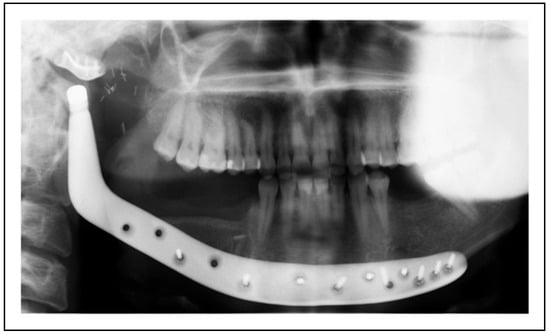

Extended Total Temporomandibular Joint Replacement—A Feasible Option for Functional and Aesthetic Reconstruction of Mandibular Defects Involving the Temporomandibular Joint

Case Examples

- Two-stage regime with simultaneous bone graft, patient 5

Two-Stage Regime, Patient 1

Single-Stage Regime, Patient 10

Bilateral TMJ Replacement With Complete Replacement of the Mandible, Patient 8